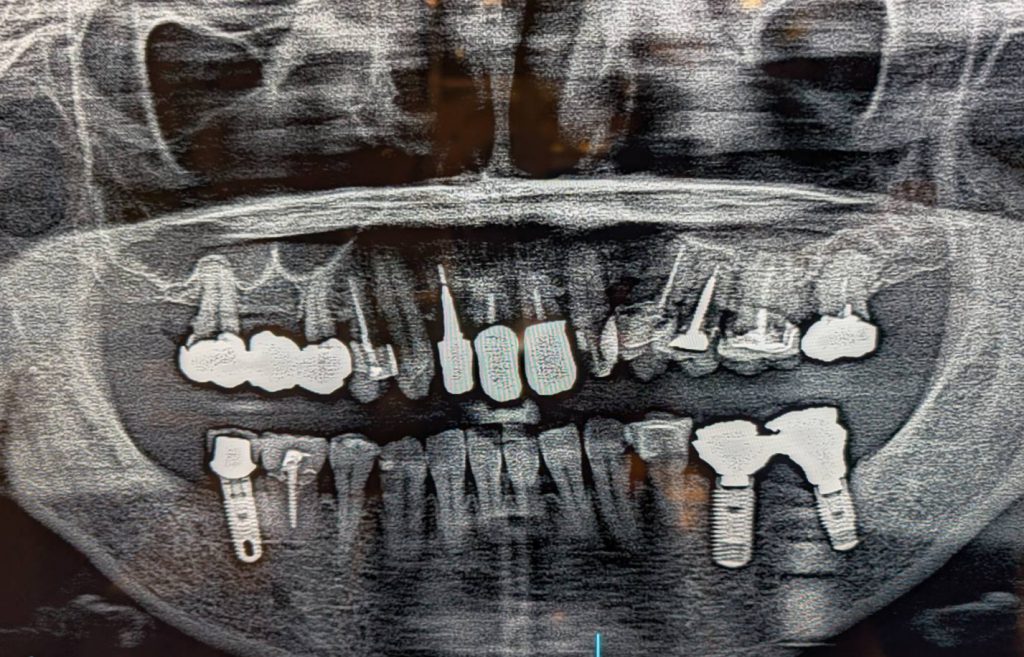

・上顎が総義歯、下顎が両側大臼歯欠損の状態で噛み合わせのバランスが崩れていました。

●上の総義歯(入れ歯)を安定させるためには、下の大臼歯部でしっかりと「噛む力」を受け止めなければなりません。

そこで、左右の奥歯にインプラントを埋入し、安定した土台を作る計画を立てました。

左右の大臼歯にインプラントを埋入しました。これにより、しっかりと力を受け止める土台が完成しました。